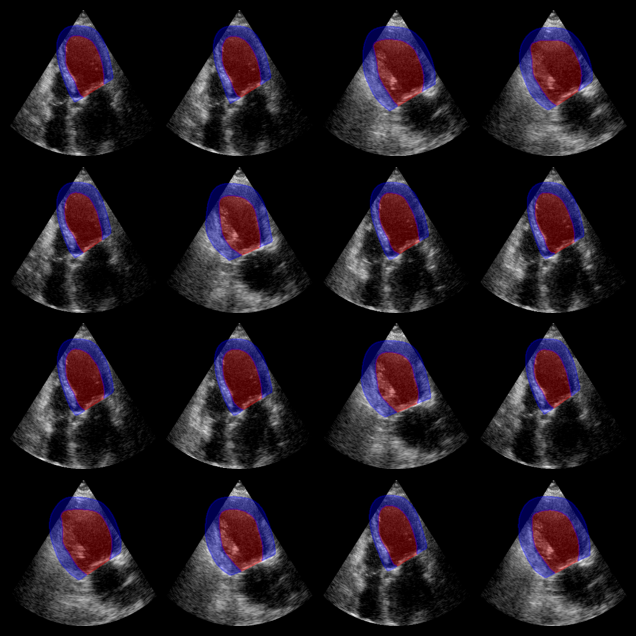

EchoNetDynamic segmentation results:

The red overlay shows the predicted left ventricle mask for each image.

EchoNet-Dynamic Example Output

# Visualization: show both LV (label 1) and myocardium (label 2)

fig, _ = plot_image_grid(batch_np, vmin=-1, vmax=1)

axes = fig.axes[:n_imgs]

for ax, mask in zip(axes, masks_camus):

# LV: label 1, Myocardium: label 2

plot_shape_from_mask(ax, mask == 1, color="red", alpha=0.3)

plot_shape_from_mask(ax, mask == 2, color="blue", alpha=0.3)

plt.savefig("augmented_camus_seg_output.png", bbox_inches="tight", dpi=100)

plt.close(fig)

Augmented CAMUS segmentation results:

Red: left ventricle mask. Blue: myocardium mask.

Augmented CAMUS Segmentation Output